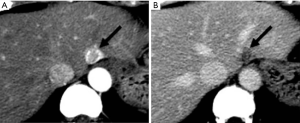

THED

THED indicate transient increased attenuation or signal intensity differences during the HAP, which return to normal or near-normal in the portal venous phase (PVP) and equilibrium phase. It typically manifests as a peripheral, wedge or cone shaped area with a straight margin, and contains normal vessels (Figure 3). THED usually occur in functional HAPS (transsinusoidal shunts and transplexal shunts) caused by decreased portal or hepatic venous flow due to contrast material passage from the high-pressure arterial blood into a low-pressure portal vein branch, thus enhancing a focal area of the liver before the adjacent parenchyma is enhanced through flow from the normal portal venous system (18,19).